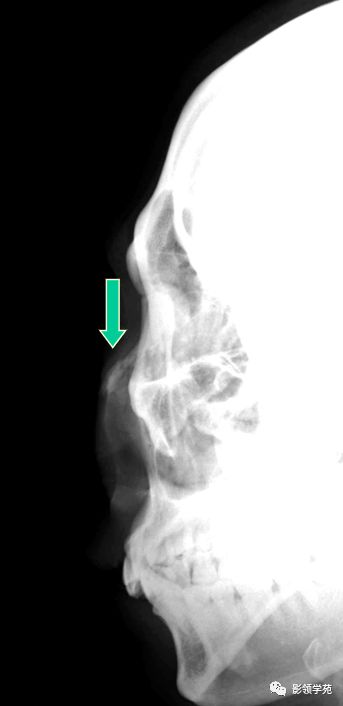

鼻骨正常侧位